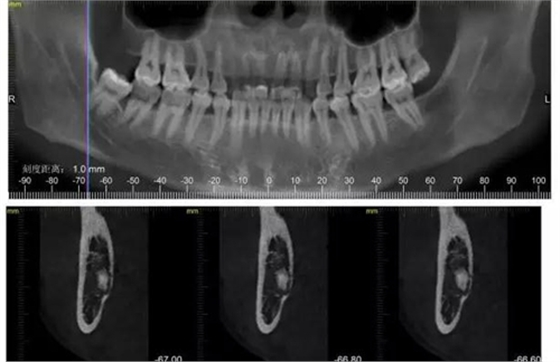

下面CBCT,可以看到兩個(gè)牙根的根尖三分之一在神經(jīng)管里面。

CBCT神經(jīng)管標(biāo)線,可以看到標(biāo)線不能連續(xù),中間被阻斷。